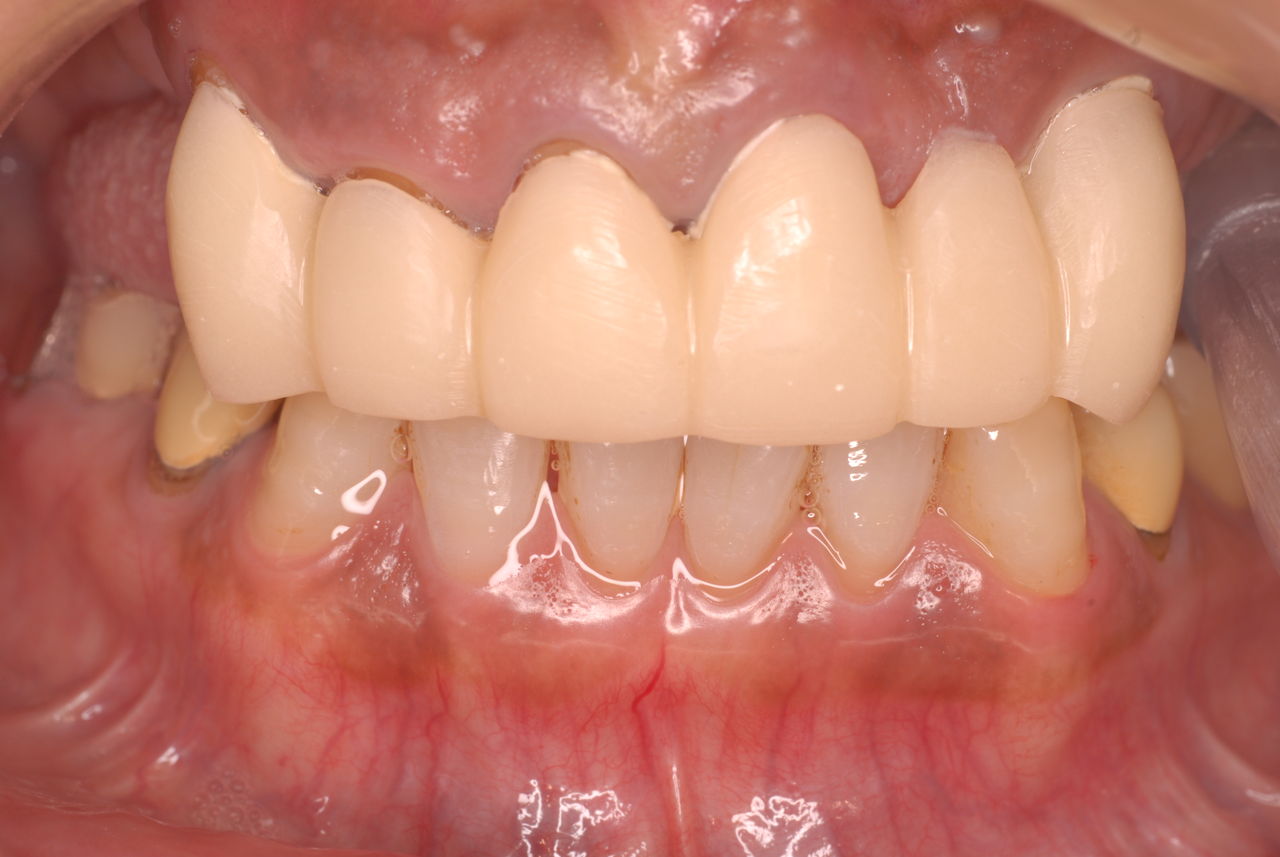

下記はおそろしいほど分析力の強い家族の方が連れてこられた患者さんの治癒例です。

取り返しのつかない変な治療を受けずにまっすぐにこちらに来られたから当方も楽でした。

これが歯や顎をいじったり、長期にマウスピースを装着していると絶望的になります。